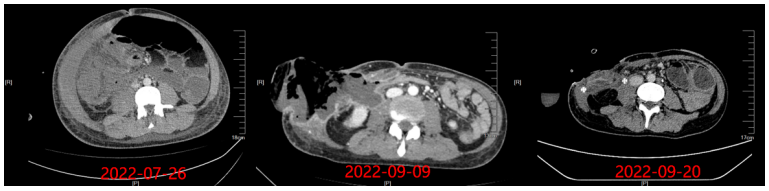

8月25日停用达托霉素,由于当时艾沙康唑暂时不可及,所以使用了两性霉素B胆固醇硫酸酯250 mg/d+亚胺培南抗感染。8月29日腹部MRI平扫+增强+弥散加权成像(DWI):右侧中下腹腔内(以右半结肠为中心)邻近前腹壁-腹膜后巨大边缘环形强化病灶,范围较前稍进展(图7),考虑升结肠缺血坏死,感染较前稍进展,并肠瘘可能。图7 腹部MRI平扫+增强+DWI(2022-08-29)第二次MDT(8月29日):血液科、感染科、普外科、消化科、麻醉科、营养科、临床药学科。MDT意见:患者目前有手术指征,但手术风险极高,预后极差,且费用高昂,继续积极抗感染治疗。患者体温36℃,腹胀腹痛较前稍缓解,可解少量大便,肠梗阻解除,生命体征平稳,转回血液科继续治疗。抗感染:哌拉西林他唑巴坦,两性霉素B胆固醇硫酸酯+艾沙康唑200 mg q8h(第3天开始200 mg qd)。9月2日, 患者体温36.7℃, 全腹胀痛好转, 右下腹皮肤溃烂黑痂, 范围约7 cm×8 cm, 局部破溃渗液(图8)。9月4日晚患者再次出现发热,体温38.3,将哌拉西林他唑巴坦改为亚胺培南+万古霉素抗感染。查血常规:白细胞13.12×109/L,中性粒细胞绝对值11.43×109/L;降钙素原3.57 ng/ml。分泌物细菌(真菌)培养:鲍曼不动杆菌(多重耐药)。9月5日腹部MRI平扫+增强+DWI: 右侧中下腹腔内(以右半结肠为中心)-邻近前腹壁-腹膜后巨大边缘环形强化病灶较前向外膨出、范围较前缩小(图9),考虑升结肠-邻近小肠及腹壁缺血坏死并感染, 肠瘘形成可能, 肠梗阻较前改善。图9 腹部MRI平扫+增强+DWI(2022-09-05)9月9日患者右下腹坏死物膨出,边缘进一步破溃,脱落,暴露腹腔内容物(图10)。在2019年ECMM发布的《毛霉病诊断和管理全球指南》中,指南小组强烈支持,除全身抗真菌治疗外,在可能的情况下,应尽早完成毛霉病的外科治疗。如有需要,应反复行切除或清创术。第三次MDT(9月9日):感染科、普外科、麻醉科、营养科、消化科、烧伤科、ICU、康复科。MDT意见考虑:患者有手术指征,但手术风险极高,需要多学科联合手术同时进行;尽快完善全腹部CT+腹部血管CTA,完善术前高风险谈话及手术/麻醉评估,患者及家属手术意愿强烈可考虑充分术前准备后手术。9月9日腹部CT+腹部血管CTA:肝中动脉瘤;腹主动脉+肠系膜上、下动脉+肾动脉CTA未见异常。9月10日行腹壁坏死组织切除+回肠部分切除+回肠造瘘+肠粘连松解术,术后转ICU观察。术中见:右下腹一13 cm×13 cm坏死腹壁与肠管组织,与周围组织无粘连,予以取出,回盲部、部分乙状结肠、右侧上段输尿管包裹在腹壁坏死组织中(图11)。病理组织活检:骨骼肌及肠壁可见大量真菌菌丝、孢子及细菌菌团,且部分真菌菌丝及孢子似位于脉管内,倾向侵袭性真菌病并广泛播散;见阑尾组织显著急性坏疽性阑尾炎,阑尾管壁及管腔内见真菌菌丝及孢子。9月14日患者生命体征平稳,无发热,为求坏死腹壁修复,转入烧伤科继续治疗。9月15日患者生命体征平稳,胆仍有腹痛、腹胀,转入胃肠外科治疗,后续进食半流质,腹痛缓解,造瘘处有排便排气。术后持续予以两性霉素B胆固醇硫酸酯+艾沙康唑治疗。9月20日腹部增强CT示(图12):“腹壁坏死组织切除+回肠部分切除+回肠造瘘+肠粘连松解术”术后改变,右中下腹术区少量渗出、积液;左侧回肠造瘘口近端小肠积液、积气扩张;右侧输尿管上段继发右肾及输尿管上端轻度积水同前;盆腹腔脓肿较前吸收。肠腔内高密度影,造影剂残留?肝中动脉动脉瘤较前增大。肝脏多发低密度灶同前,仍考虑小脓肿形成可能。9月22日,患者生命体征平稳,复查骨髓形态及流式均未见异常细胞。11月1日,烧伤整形科于全麻下行"右腹壁腹膜补片修补+腹壁缺损右股前外侧皮瓣转移修复术"。术前已停用两性霉素B,予以艾沙康唑口服维持治疗。2024年1月3日随访腹部CT提示患者恢复较好(图13)。